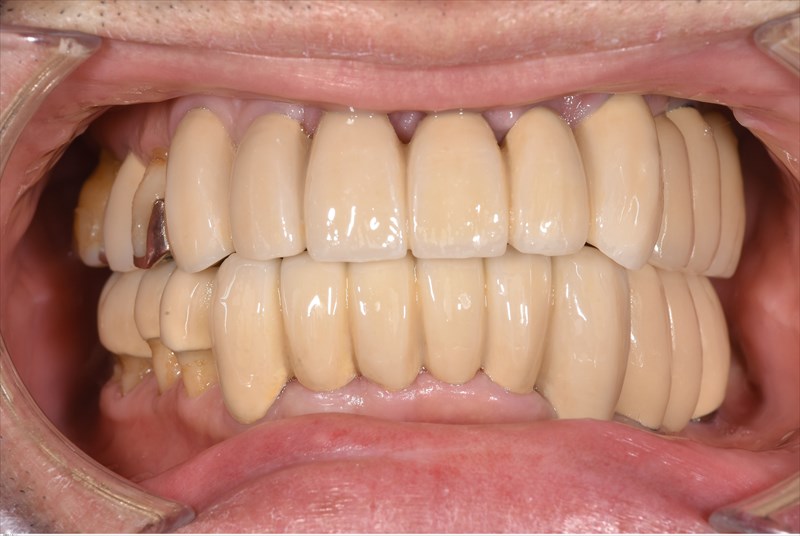

歯周病治療後3年経過の写真です

メンテナンスの効果もあり1本も歯を失っていません。